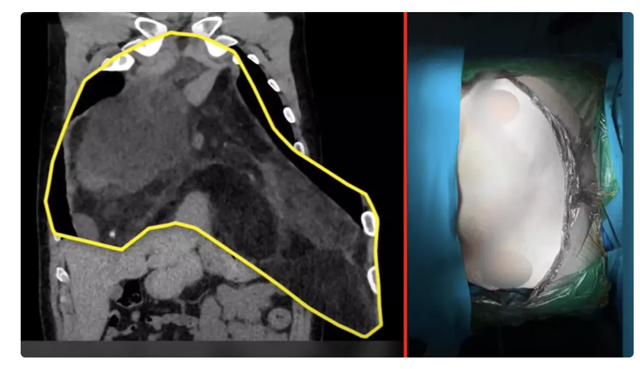

“Çap olarak 47 santim boyunda ve 4 kilo ağırlığında bu çapta Türkiye'de bilinen ve bildirilen en büyük vaka. Artı dünyada da sayılı 1-2 vakadan birisi. Hastalığı aslında bir göğüs akciğer boşluğundaki bir kitleydi. Oldukça hızlı büyüyen ve göğsünün içinde çok ciddi yer kaplayan bir tümördü.

Yandan yapılan torukotomi dediğimiz kesiyle de yapma imkanımız yoktu. Çünkü bu kitle akciğerin sağından başlıyor, kalbi eziyor ve oradan da sol akciğerin tamamını dolduruyordu. Yani göğüs kafesini sağdan sola açıp bu iman tahtası dediğimiz sternum kemiğinde keserek göğsü kaldırarak yapıyoruz. Sonucumuz başarılı oldu.”

"Şok geçirdim! İçimden bir yaratık çıkmış resmen"

Özgürel’de hastalığının ne denli büyük olduğunu operasyondan çıkınca öğrendi. Özgürel açıklamasında “Ben onu 26 santim biliyordum. Çıktığında öğrendim 47 santim olduğunu. Bütün PET çekiminde, MR'larda falan hep 26 santimlik bir kitle var diye söyleniyordu. Şok geçirdim. İçimden bir yaratık çıkmış resmen.” dedi.